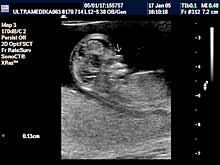

A) I trimestar do 14

nedelje gestacije

(3 meseca + 2 nedelje)

Indikacije za ultrazvučni pregled:

- Izostanak menstruacije, procena vitalnosti rane trudnoće,

procena materične i/ili postojanje vanmaterične trudnoće.

(Od 4-7 nedelje gestacije, ili prva 2 meseca od prvog dana zadnje

menstruacije).

- GENETSKI SONOGRAM (2 - 3 ½ meseca):

- Otkrivanje ultrazvučnih markera na postojanje hromozomskih

anomalija ploda (SKRINING na ANEUPLOIDIJE). Ovaj genetski sonogram

treba uraditi dva puta u intervalu od 9 do 14 nedelje gestacije uz

biohemijsku proveru iz krvi trudnice nakon tačne ultrazvučne procene

veličine ploda. Genetski sonogram sam isključuje oko 88% trizomija,

a udružen sa biohemiskim analizama se isključuje oko 98%

aneuploidija.

- Prva procena i otkrivanje krupnih anatomskih anomalija ploda

koje ne moraju pratiti hromozomske anomalije.

- Prva procena posteljične cirkuacije Broandband - CD

- Pregled materice i organa male karlice kao i organa abdomena

trudnice.